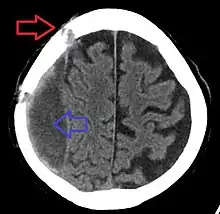

| Subdural hematoma as marked by the arrow with significant midline shift | |

Subdural hematomas occur most often around the tops and sides of the frontal and parietal lobes.[3][2] They also occur in the posterior cranial fossa, and near the falx cerebri and tentorium cerebelli.[3] Unlike epidural hematomas, which cannot expand past the sutures of the skull, subdural hematomas can expand along the inside of the skull, creating a concave shape that follows the curve of the brain, stopping only at dural reflections like the tentorium cerebelli and falx cerebri.

On a CT scan, subdural hematomas are classically crescent-shaped, with a concave surface away from the skull. However, they can have a convex appearance, especially in the early stages of bleeding. This may cause difficulty in distinguishing between subdural and epidural hemorrhages. A more reliable indicator of subdural hemorrhage is its involvement of a larger portion of the cerebral hemisphere. Subdural blood can also be seen as a layering density along the tentorium cerebelli. This can be a chronic, stable process, since the feeding system is low-pressure. In such cases, subtle signs of bleeding—such as effacement of sulci or medial displacement of the junction between gray matter and white matter—may be apparent.